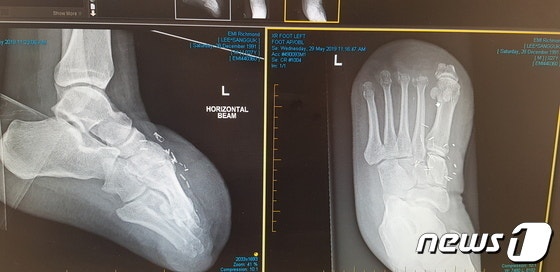

다쳐서 병원갔는데 너 없는 사이 증거조작 해버리면 나처럼 4년에 걸쳐서 누명 벗거나 자기안전 부주의 했다는 누명 쓰게 된다 다들 조심해~

조심해라 정신적으로 휴유증 있어서 다시는 기관장 못한다고 양형부당 주장한 기관장 2심도 시작안했는데 다시 배타러 갔다 ;;;

58년생 기관장이면 조심해라 잘못하면 장애인 됨

조심해라 정신적으로 휴유증 있어서 다시는 기관장 못한다고 양형부당 주장한 기관장 2심도 시작안했는데 다시 배타러 갔다 ;;; 58년생 기관장이면 조심해라 잘못하면 장애인 됨

30이 배 탔으면 오폴 출신이야? 근데 40미터에서 크로스헤드 베어링이어떻게 떨어지냐? 사진봐도 챔버안 같은데 일기사는 사람 새끼냐? 힌달된 삼기사 챔버에 집어넣고 - dc App